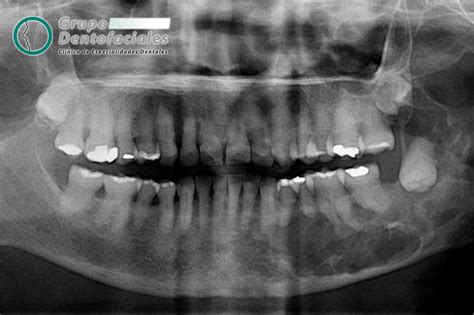

Esto es una tranquilidad. La muela del juicio no está. El segundo molar está sano y no está acosado por un tercer molar caprichoso y endemoniado.